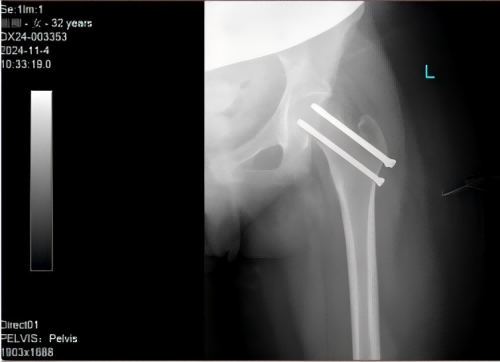

空心钉固定术后X片

考虑到患者为妊娠晚期,骨折位于髋部且疼痛剧烈,此类骨折为急诊手术指征,处理不当或不及时,将影响产妇正常分娩进而危及胎儿安全。于是,在骨关节与运动医学科科主任王靖的指挥下,贾真副主任医师团队联合产科陆佳黛总住院医师和麻醉科黄倩副主任医师组成MDT多学科协作团队。经多学科讨论后为患者实施了单次腰麻下骨折闭合复位内固定术,这种微创手术仅用几颗空心钉将骨折处固定,仅留3cm大小的伤口,创伤小、恢复快。此手术和麻醉方式对患者及胎儿影响最小,由于手术及时,也能最大程度上降低骨折相关并发症的发生。